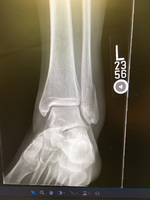

Gallery :: 2023 :: May